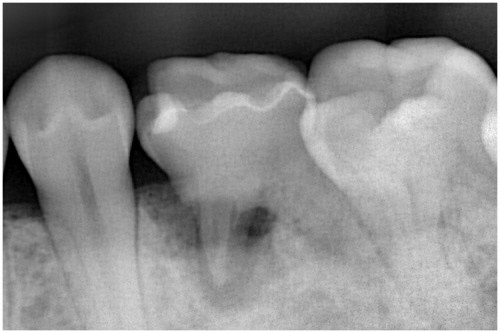

根の先に病巣ができています。

かぶせ物と土台を外します→根の管に詰まっている薬を外します→再び根の管を拡げます

根の管を拡げ終えました→症状がなくなりました→最終的なお薬を詰めます

土台の型を取ります→土台を付けます

歯の周りを削ります→被せ物を付けます